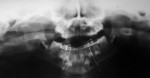

Nineteen patients between the ages 3 and 12 years with maxillofacial injuries (Figure 1 and Figure 2) presented to the Department of Pedodontics and Preventive Dentistry in K D Dental College and Hospital, Mathura, India. Detailed case histories, clinical examinations, and radiographic investigations such as orthopantomography, occlusal radiography, and intraoral periapical radiography were performed (Figure 3 through Figure 8). After careful evaluation, a diagnosis of the type of fracture was made and a treatment plan was formulated for each patient. Informed consent was obtained from the parent, and in some cases, treatment was performed under general anesthesia, with written consent obtained from the parent.

In all patients, splints and arch bars were removed after 2 to 4 weeks. Postoperative radiographs were obtained to confirm the healing of the fractured site before removal of the splint (Figure 5 and Figure 8), and all the patients were followed-up for 12 months. None of the patients had complications in the postoperative period, and uneventful healing and union of the fracture segment occurred in all patients. In one patient, healing time was prolonged because of continuous dislodgement of the splint, which was re-cemented. A slight discrepancy in the occlusion in a few patients was observed, which was corrected on its own over the course of time.